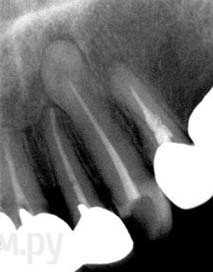

ger_berra Опубликовано 28 ноября, 2013 Поделиться Опубликовано 28 ноября, 2013 http://s57.radikal.ru/i157/1311/85/ff0a2ad052a3.jpg http://s020.radikal.ru/i710/1311/4f/b26673959429.jpg http://s55.radikal.ru/i149/1311/5c/211cff45a918.jpg 12 Ссылка на комментарий

АнтонТЛТ Опубликовано 28 ноября, 2013 Поделиться Опубликовано 28 ноября, 2013 Красиво Мне кажется там дельта Ссылка на комментарий

ger_berra Опубликовано 28 ноября, 2013 Автор Поделиться Опубликовано 28 ноября, 2013 Красиво Мне кажется там дельта Да,Антон,я тоже так подумала.Потому что десятка упиралась и далее не резала.Пыталась подогнуть,но тщетно.... Просто позвенела хлорку Ссылка на комментарий

Kivilgar Опубликовано 28 ноября, 2013 Поделиться Опубликовано 28 ноября, 2013 Вот еще один довод в непросверливание апекса ради "красивой" картинки. 6 Ссылка на комментарий

ger_berra Опубликовано 28 ноября, 2013 Автор Поделиться Опубликовано 28 ноября, 2013 (изменено) Апексочек.jpgДаже в данном кейсе?Даже и здесь.КТ тут сильно интересно. Изменено 28 ноября, 2013 пользователем ger_berra Ссылка на комментарий